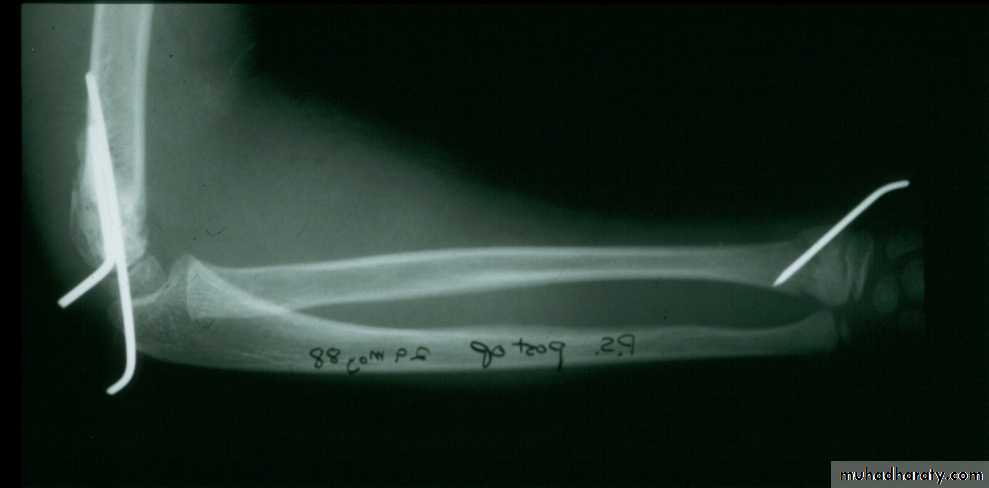

when I was a resident !!6 y.o. sustained this FX. NV intact.

Following obtaining a satisfactory closed reduction how do you propose to stabilize it?• Medial-lateral pins

6 y.o. sustained this FX. NV intact.

Following obtaining a satisfactory closed reduction how do you propose to stabilize it?Multiple lateral pins

Outside fracture line ?6 y.o. sustained this FX. NV intact.

Following obtaining a satisfactory closed reduction how do you propose to stabilize it?

Cross pinsantegrade lateral

Five y.o. male with this fracture pattern

• Following obtaining a satisfactory closed reduction how do you propose to stabilize it?Multiple lateral pins

Stable ??Five y.o. male with this fracture pattern

• Following obtaining a satisfactory closed reduction how do you propose to stabilize it?

Medial-lateral

retrograde cross pinsDifficult and unstable